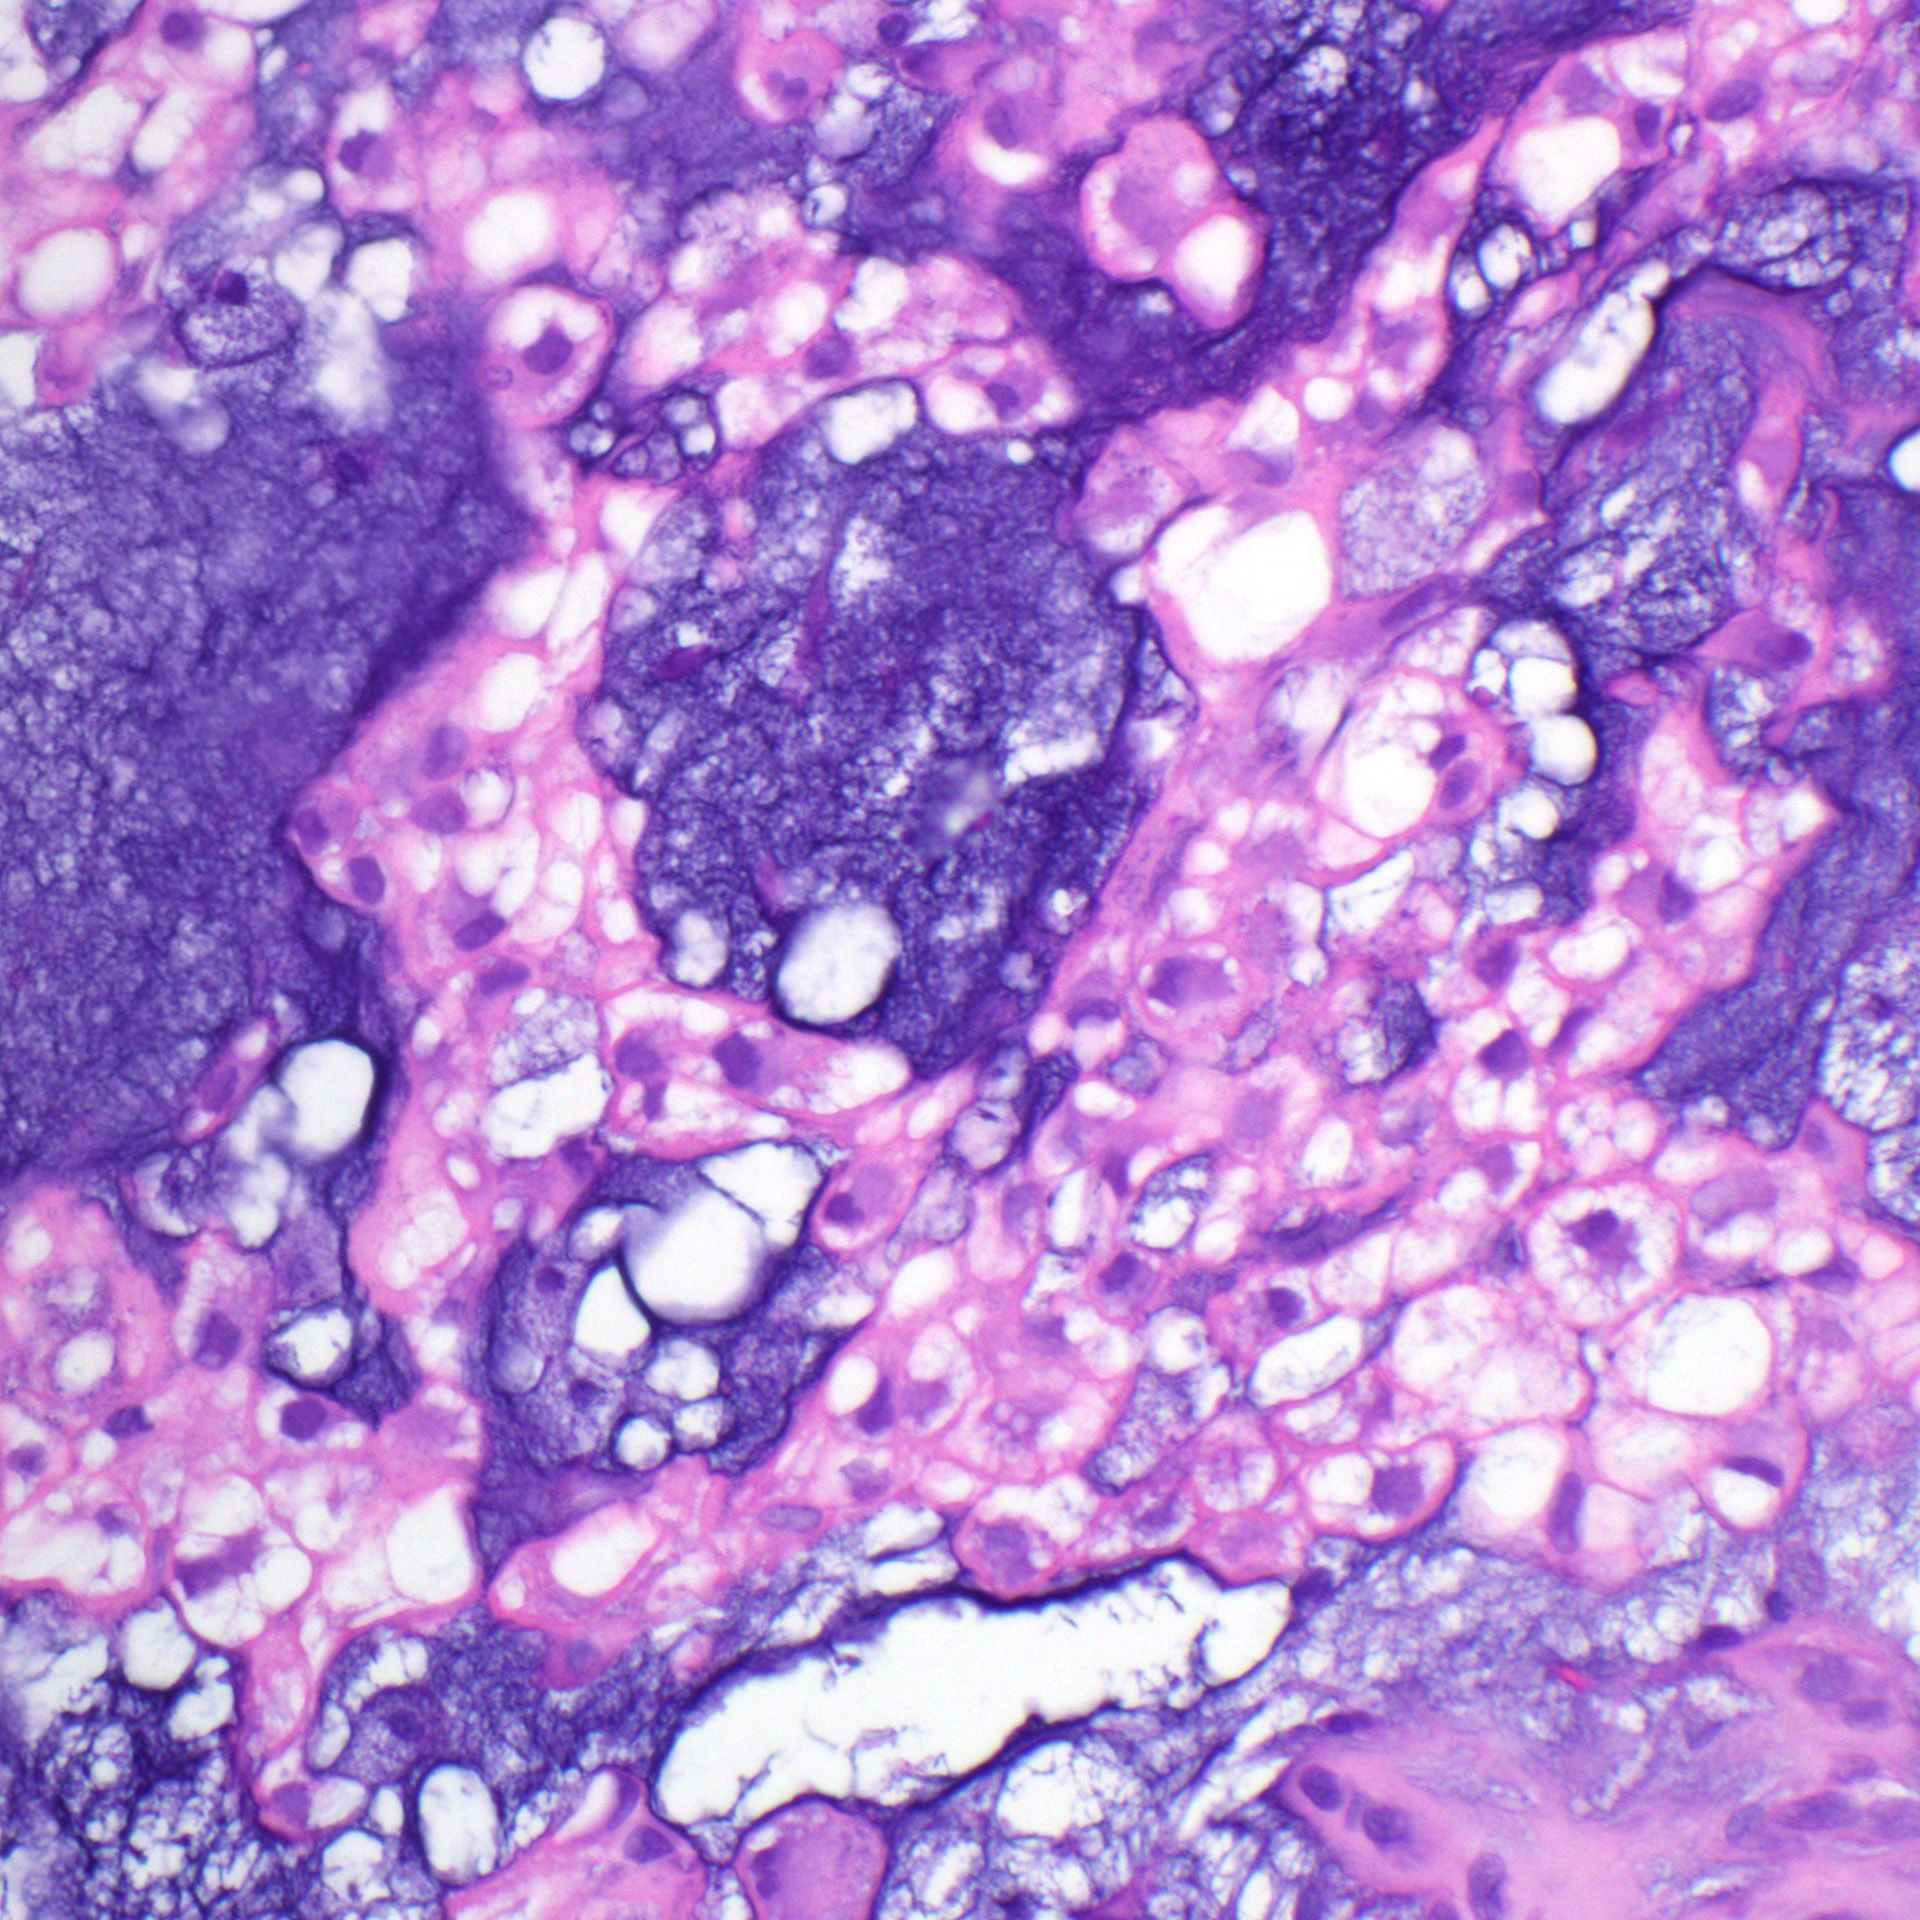

What process is happening here? How old is this patient?

Answers & pics w labels: kikoxp.com/posts/20899